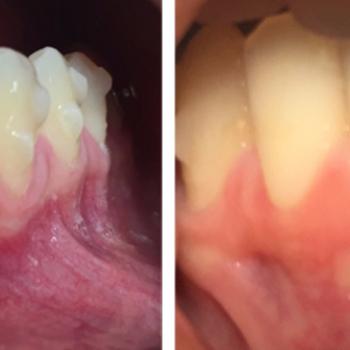

La cirugía mucogingival reconstructiva alrededor de implantes corrige los defectos de la morfología, posición y/o cantidad de encía queratinizada alrededor de los mismos. El documento que mostramos a continuación presenta el caso clínico de un paciente varón de 55 años de edad, exfumador de hace 2 años, con antecedentes de periodontitis crónica moderada generalizada y avanzada localizada tratada y, actualmente en fase de mantenimiento. El paciente no refería ningún antecedente médico de interés odontológico ni alergias conocidas.

El caso clínico es un buen ejemplo de cómo dotar de una buena cantidad de encía queratinizada unos implantes dentales con una emergencia en mucosa alveolar. De esta forma puede mejorarse la higiene periimplantaria diaria y disminuir así  las posibilidades de aparición de patología periimplantaria en un futuro.